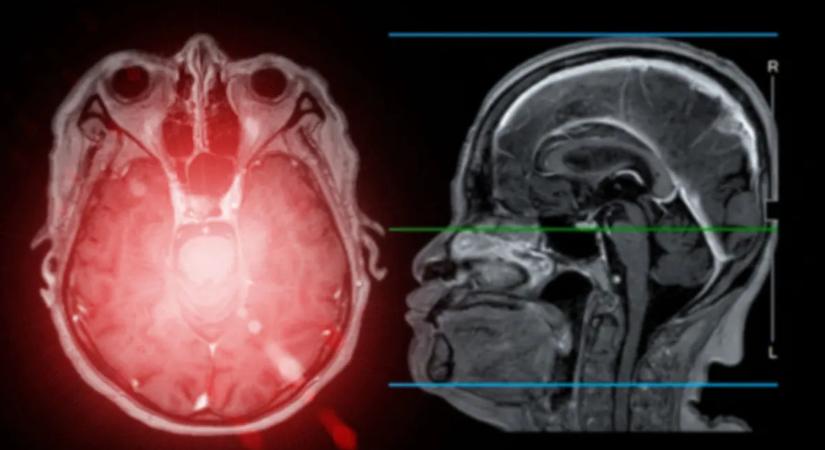

Horror: emberben még sosem látott parazita okozott memóriazavart egy nőnél